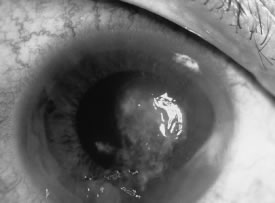

of filamentous fungi but are not absolute requisites for infection. The principal risk factors for yeast or Candida keratitis are protracted epithelial ulceration, penetrating keratoplasty, and therapeutic soft contact lens wear. Concurrent administration of topical corticosteroids enhances the replication of Candida through suppression of the host inflammatory response. Although polymicrobial keratitis is uncommon, risk factors for Candida are comparable to bacterial keratitis, and Candida is the most common genus among mixed bacterial and fungal keratitis.26,27 Polyfungal keratitis is rare.14 The distinct biomicroscopic signs of infectious microbial keratitis are epithelial and stromal ulceration (vs. intact epithelium), necrotizing stromal inflammation (vs. nonnecrotizing inflammation), and single location (vs multifocal sites) of the stromal inflammation. These distinctive signs are determined by the strain (virulence) of the responsible organism(s); the mechanism of inoculation into the cornea; the time interval from inoculation to examination; the antecedent status of the cornea; antimicrobial or corticosteroid therapy; and other host factors, such as an ocular surface abnormality, tear dysfunction state, lid closure dysfunction, and immunosuppression. Other biomicroscopic signs are helpful in judging the severity of the inflammatory process but not the presence or type of infection. These include epithelial edema, stromal edema, loss of endothelial reflectivity (pseudoguttata), endothelial plaque, aqueous flare and cells, and hypopyon. In the early stages of infection, filamentous fungi produce signs that are readily distinguishable from yeast or bacterial keratitis. The most distinctive sign is the presence of delicate, fine, feathery, opalescent, gray-white or yellow-white material in the anterior stroma, surrounded by scant cellular infiltrate or edema (Fig. 1). The epithelium may be intact. The overlying epithelium may be granular and the surface elevated and irregular in contour. Linear infiltrates typically extend into the adjacent stroma. Multiple discrete opacities may develop outside the perimeter of the principal focus of inflammation, either separated by clear stroma or linked by fine linear collections of inflammatory cells and material (Figs. 2 and 3). In the absence of inflammation in the adjacent stroma, branching hyphal fragments may be visualized by biomicroscopy (Figs. 4 and 5). Confocal microscopy may also detect hyphal elements within the stroma.28,29 Peripheral infection resembles noninfectious marginal infiltrative and ulcerative keratitis (Fig. 6). Multifocal keratitis may develop after contact lens wear or injury by multiple projectiles (Fig. 7). In the early stages, iritis is present and the intraocular pressure remains normal. Inappropriate, empirical therapy of fungal keratitis with topical fluoroquinolone or aminoglycoside antibiotics may suppress or eliminate the superficial elements but allow extension of the organisms into the stroma because these agents may possess selective antifungal activity.4,30,31

There is no distinguishing clinical sign by which to recognize the genus or species of the infectious filamentous fungus. F. solani is the most virulent organism and typically produces rapidly progressive infection characterized by epithelial and stromal ulceration, dense stromal necrosis, abundant cellular infiltrate, and edema in the adjacent stroma and hypopyon (Figs. 8 and 9). Delicate feathery components are transient. Individual hyphal fragments are rarely visualized. Infection by certain species of Aspergillus and Scedosporium (Figs. 10 and 11) resembles F. solani keratitis and progresses rapidly. Infection by less virulent organisms, such as Curvularia and Alternaria species, produces small, focal (less than 3-mm diameter) areas of nonnecrotizing stromal inflammation with delicate feathery borders (see Fig. 1 and Fig. 12). Macroscopic pigmentation may develop in keratitis caused by Alternaria, Curvularia, and other dematiaceous fungi (Fig. 13).4,11,14 The central component may progress to dense, opaque, gray-white suppuration in the deep stroma without enlargement in total area and may be accompanied by mild inflammation in the adjacent stroma. Iritis is minimal to moderate. Infection caused by other, relatively less virulent organisms resembles herpes simplex or noninfectious keratitis (Fig. 14).